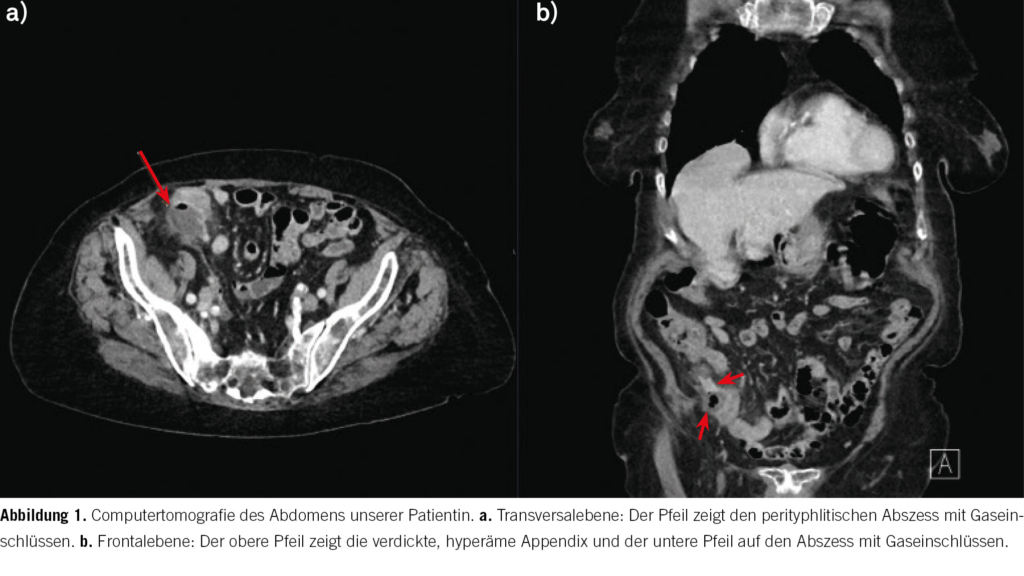

Zur Suche eines möglichen Infektfokus erfolgte aufgrund der Druckdolenz im Unterabuch eine Computertomografie des Abdomens. Hierbei zeigte sich der Verdacht auf eine gedeckt perforierte Appendizitis mit perityphlitischer Abszedierung und beginnender Peritonitis (Abb. 1). Aufgrund des hohen Patientenalters wurde in Rücksprache mit den Kolleginnen und Kollegen der Viszeralchirurgie auf eine notfallmässige Appendektomie verzichtet. Nach Abnahme von Blutkulturen wurde mit einer intravenösen antibiotischen Therapie mit Amoxicillin/Clavulansäure begonnen. Am Folgetag erfolgte durch die interventionellen Radiologen eine perkutane Drainageeinlage in den perityphlitischen Abszess. Darunter kam es zu einer raschen Besserung der Schmerzsymptomatik und die Entzündungsparameter waren rückläufig. In den Kulturen der Abszess-Drainage wurden pansensible Escherichia coli nachgewiesen. Unter einer parenteralen antibiotischen Therapie mit Amoxicillin/Clavulansäure kam es zu einer Normalisierung der Leuko- und Thrombozyten. Bei weiter persistierender makrozytärer Anämie konnte in der weiteren Diagnostik ein schwerer Vitamin-B12-Mangel von 71 pmol/l (141–189 pmol/l) nachgewiesen werden. Es wurde mit einer parenteralen Substitution begonnen.

Bei unserer hochbetagten Patientin wurde computertomografisch eine komplizierte Appendizitis mit perityphlitischem Abszess diagnostiziert. Die eingeleitete konservative Therapie mit Abszess-Drainage und antibiotischer Therapie mit Amoxicillin/Clavulansäure war erfolgreich.